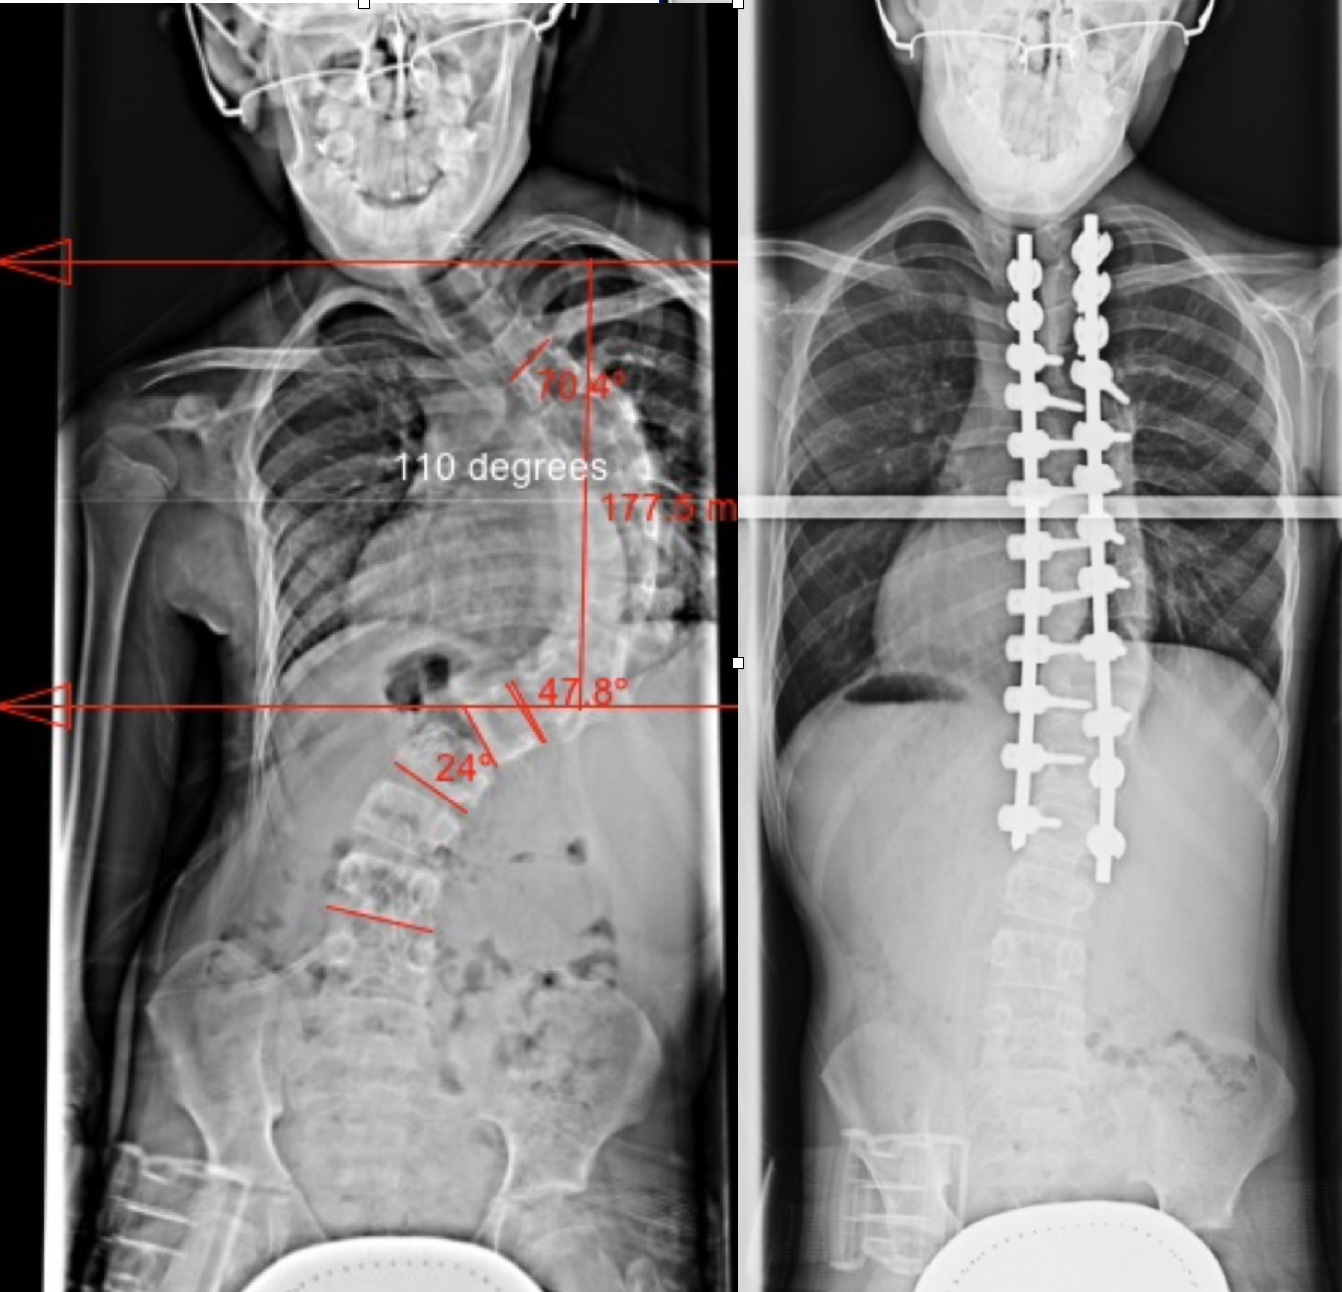

Scoliosis surgery, before and after. – MEDizzy Journal

Xrays before and after spinal fusion surgery for scoliosis : medizzy